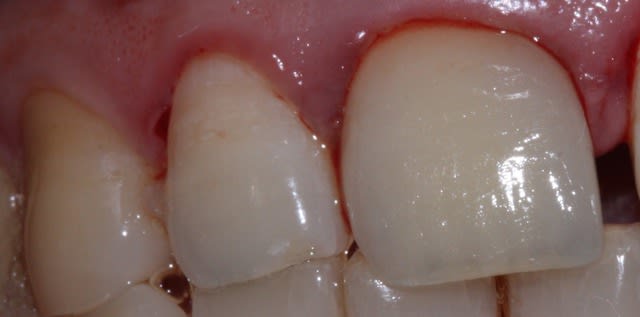

+1 sethef...fêlure très probable (vu l'aspect de la gencive je penche dans la zone mésio-vestibulaire) et qui serait bien en accord avec le passé de cette dents qui c'est déjà fracturée...

Ca sent très fort la sur occ . la latérale et la canine sont presque en bout a bout, et il y a un diasteme.+ plus une paro pas très belle . l angle distal de ta centrale est trop verrouillant .si le tenon n est pas tordu ,ce n est pas la peine de tout reprendre , il suffirait d équilibrer . a ce propos je ne comprend pas pourquoi c est le labo qui te l a équilibré ? S' ils savaient le faire ca se saurait.

C'est sûre qu'en occluso c'est pas favorable (les incisives semblent participer à la latéralité) ... Si la rétention de la couronne et de l'inlay core était mieux assurée, il y aurait eu de toute façon une fracture très rapide de la céram plutôt qu'un descellement...

Il n'y a qu'à voir la taille du tenon et celle de la couronne pour s'en convaincre. L'image parle d'elle même!